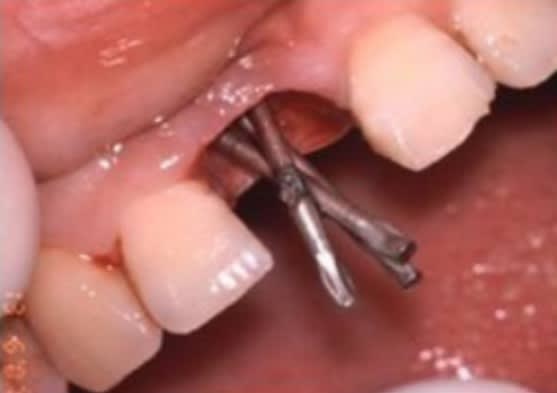

Et lĂ  c'est les Implants de Scialom En tantale puis titane : intĂ©rĂȘt on pouvait Ă©viter les structures anatomiques

Lachmar si tu regardes -> regarde la derniĂšre photo , y en a un qui a rallongĂ© un scialom 😊. Une idĂ©e de gĂ©nie ^^

D'ailleurs comment ça se mettait ? Ils les vissaient directement dans l'os ?!?!? Sans prĂ©paration avec des forĂȘts ?

sans forage, Ă  la "masse" (au maillet...;-))

... et soudure en bouche pour faire tenir la prothĂšse ... đŸ‘“đŸŽ†đŸŽ‡đŸ”©